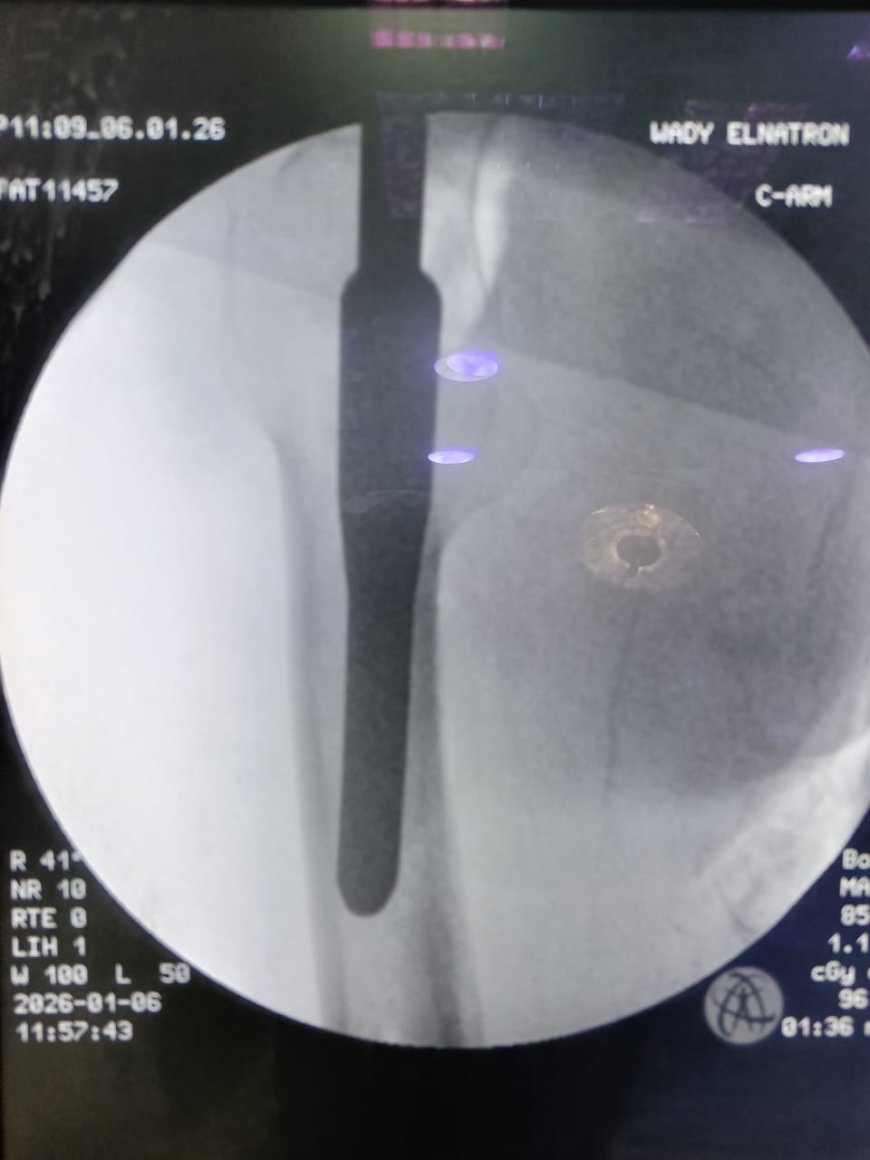

وعقب استقبال الحالة، تم إجراء التقييم الإكلينيكي الشامل والفحوصات الطبية اللازمة، وعلى ضوء النتائج تقرر التدخل الجراحي العاجل، حيث تم إجراء رد مغلق وتثبيت لكسر أعلى الفخذ الأيمن بين المدورين باستخدام مسمار نخاعي تشابكي (جاما نيل) المخصص لمثل هذه الكسور، بما يحقق ثباتًا جيدًا للكسر، ويساهم في سرعة التعافي وتقليل فرص حدوث المضاعفات.

أ/ محمد عيسى – فني الأشعة